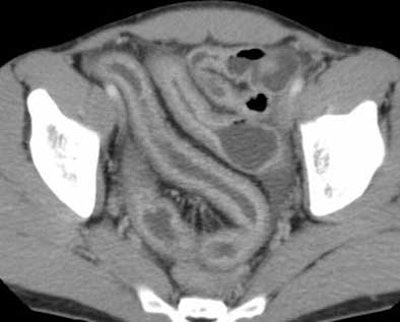

| Top and below: In same 21-year-old patient, axial CT enteroclysis shows long-segment inflammatory reaction and severe thickening of the terminal and preterminal ileum due to histologically proven Crohn's disease. Bottom image, equivalent coronal multiplanar reformation. |